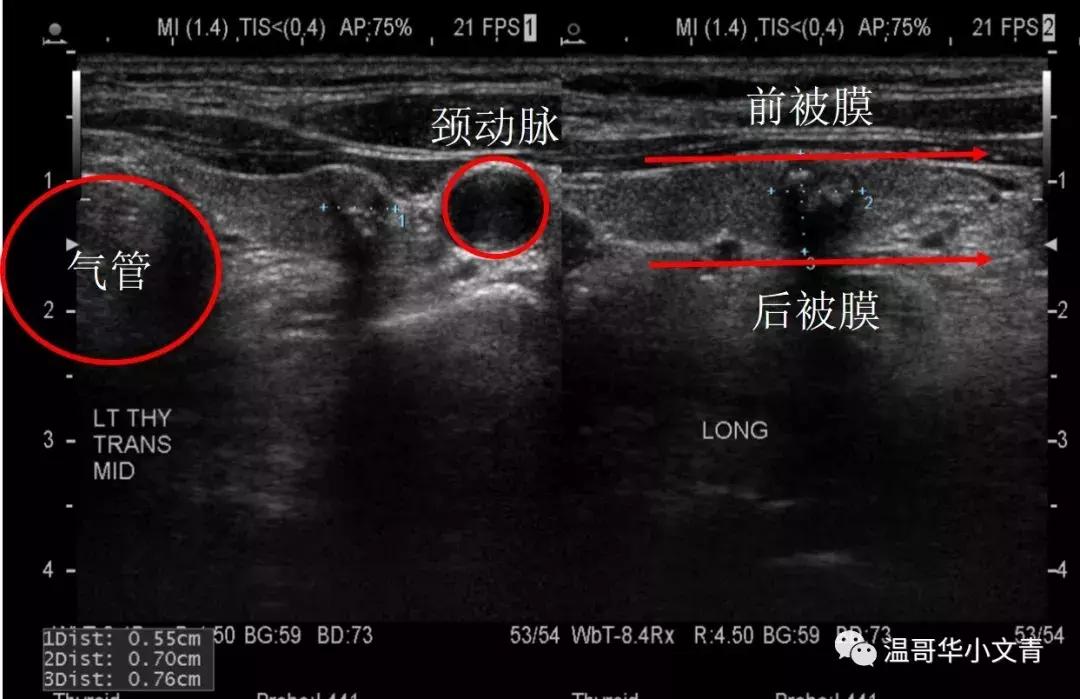

为什么这么说呢?因为甲状腺癌的第一种转移方式是向腺外侵犯,而如上图的颈部彩超恰恰最好能反应甲状腺癌和气管,颈动脉,前被膜,后被膜的关系。如果说甲状腺癌有初始的腺外侵犯,彩超是最容易发现。甲状腺癌的第二种转移方式是淋巴道转移,对于初始的淋巴结转移,通常位于气管前(上面B区),气管旁(上面C区D区),以及大血管周围,同样是彩超更为敏感。当转移灶是两三毫米的时候,精度高的彩超就能发现异常,而颈部增强CT绝大多数时候并没有这个精度。